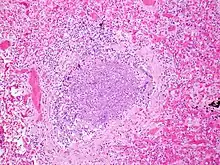

The term usually refers to acute viral bronchiolitis, a common disease in infancy. This is most commonly caused by respiratory syncytial virus[13] (RSV, also known as human pneumovirus). Other agents that cause this illness include human metapneumovirus, influenza, parainfluenza, coronavirus, adenovirus, rhinovirus and mycoplasma.[14][15]